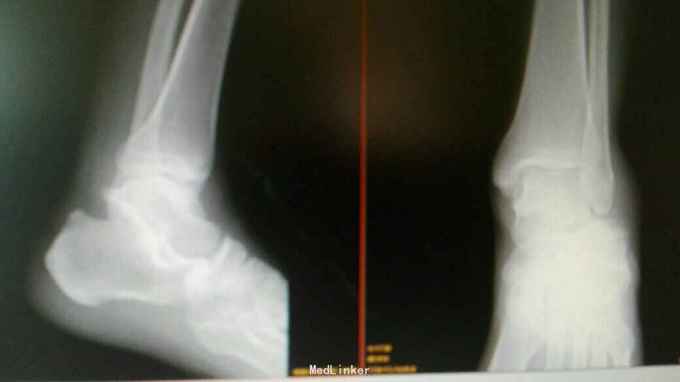

患者男,42岁,钢筋砸伤左足跟部肿痛活动受限1周。 一周前拍X线未能明确诊断,因症状无改善,再次就诊。

查体:左足跟部肿胀,外翻畸形,压痛,叩痛,活动受限。 X线:左侧距下关节外侧脱位。

诊断:左距下关节脱位 治疗:手法闭合复位。